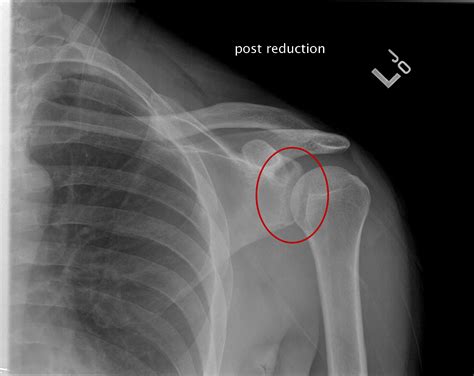

• Imaging Tests: X-rays are the primary imaging tool used to confirm the diagnosis. Additional tests such as CT scans or MRIs may be ordered to evaluate the extent of the injury and any associated damage to surrounding tissues.

• Closed Reduction: This procedure involves manually realigning the humeral head back into the shoulder socket. It is typically performed under sedation or anesthesia to minimize pain and discomfort.